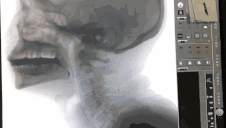

为了解决吞咽障碍问题,邵阿婆抱着试试的心理来到总院康复科求助。康复治疗师长王群和言语治疗师杨玲接诊了她,对她进行了吞咽障碍评估,从她的症状和梗死部位考虑患者的功能障碍属于吞咽障碍中的环咽咽肌失迟缓。为了明确诊断则需要用到特殊的检查方式——吞咽造影(VFSS)。这是一种在x线透视下,针对口、咽、喉、食管的吞咽运动所进行的特殊造影,可进行点片或录像来记录所看到的影像,并加以分析。检查过程中,患者需进食两种或以上性状的食物(如液体、糊状物、固体等),通过不同性状食物的进食,观察患者的吞咽运动,充分了解其进食过程及食物去向。吞咽造影的检查效果十分准确,被称为吞咽评估的“金标准”。邵阿婆的检查结果显示她在进食不同种性状的食物时环咽肌都不开放。

经过整个言语治疗团队的努力,治疗第3次后患者可以自己拿杯子喝水了,在进行7次球囊扩张术后再次为患者做了吞咽造影评估,评估结果显示液体食物可以咽下,环咽肌从之前完全不开放到目前可以开放了。邵阿婆终于可以安全进食酸奶、面类等食物,她的脸上终于露出了久违的笑容。她告诉我们:“插胃管的这些日子,真是度日如年,吞口水都呛,呛了又怕引起肺炎。现在在你们的帮助下可以吃东西了,真是开心极了。”

治疗前患者无法咽下食物

治疗后患者已毫无吞咽障碍